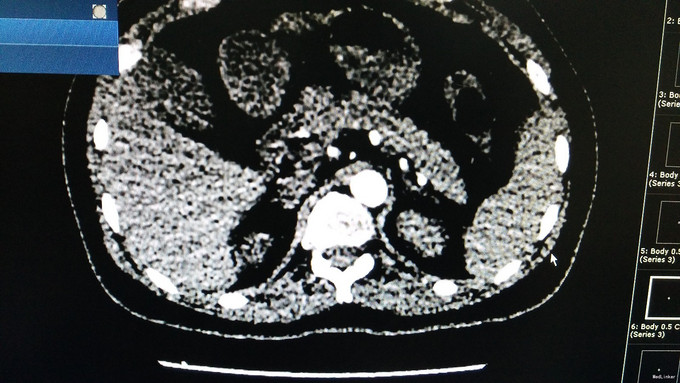

诊断为:低血糖症, .治疗:针对低血糖症:监测血糖,防止患者因低血糖发生意外。 2.针对胰腺占位性病变(胰岛素瘤可能性大):建议转入胰腺外科手术治疗,病情变化随诊。